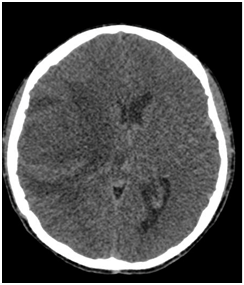

We present the case of a 16-year-old male patient, born in Veracruz Mexico with history of pulmonary stenosis, hypoplastic right ventricle, interauricular communication and patent ductus arteriosus who had surgical intervention with Blalock Taussig shunt on November of 2003. On July 11th 2016 he started with numbing of the left half of his face including the tongue, for which he didn’t seek any medical attention. On July 18th 2016 he had a generalized seizure, which lasted 10 minutes, according to his family. On July 28th 2016 he started to lose strength of the left half of his body and wasn’t able to walk or move his left arm. With these symptoms he was admitted to our hospital where he also referred headache. CT scan showed hypodense images on right temporoparietal region and reinforcement images on right parietal region suggesting brain abscesses (Figure 1 & 2). With these findings, along with the clinical presentation, the diagnosis of brain abscess was made and antibiotic treatment was started with third generation cephalosporin, metronidazole and glucopeptide. The patient was evaluated by the neurosurgery team who decided to differed surgical treatment because of the size of lesions in CT scan and improvement in next CT scan images. On August 8th 2016 a MRI (Figure 3) of the brain showed capsule formation. The patient continued with antibiotic treatment and dexamethasone in reduction dose. A new MRI of the brain, on August 29th 2016, showed abscesses of less than 3 cm, this along with the patient improving neurological state and decide no need for surgical treatment. The patient completed 61 days of parenteral treatment with ceftriaxone, metronidazole and vancomycin. The last imaging study previous to the discharge of the patient showed brain abscesses of less than 0.5 cm.

Figure 1